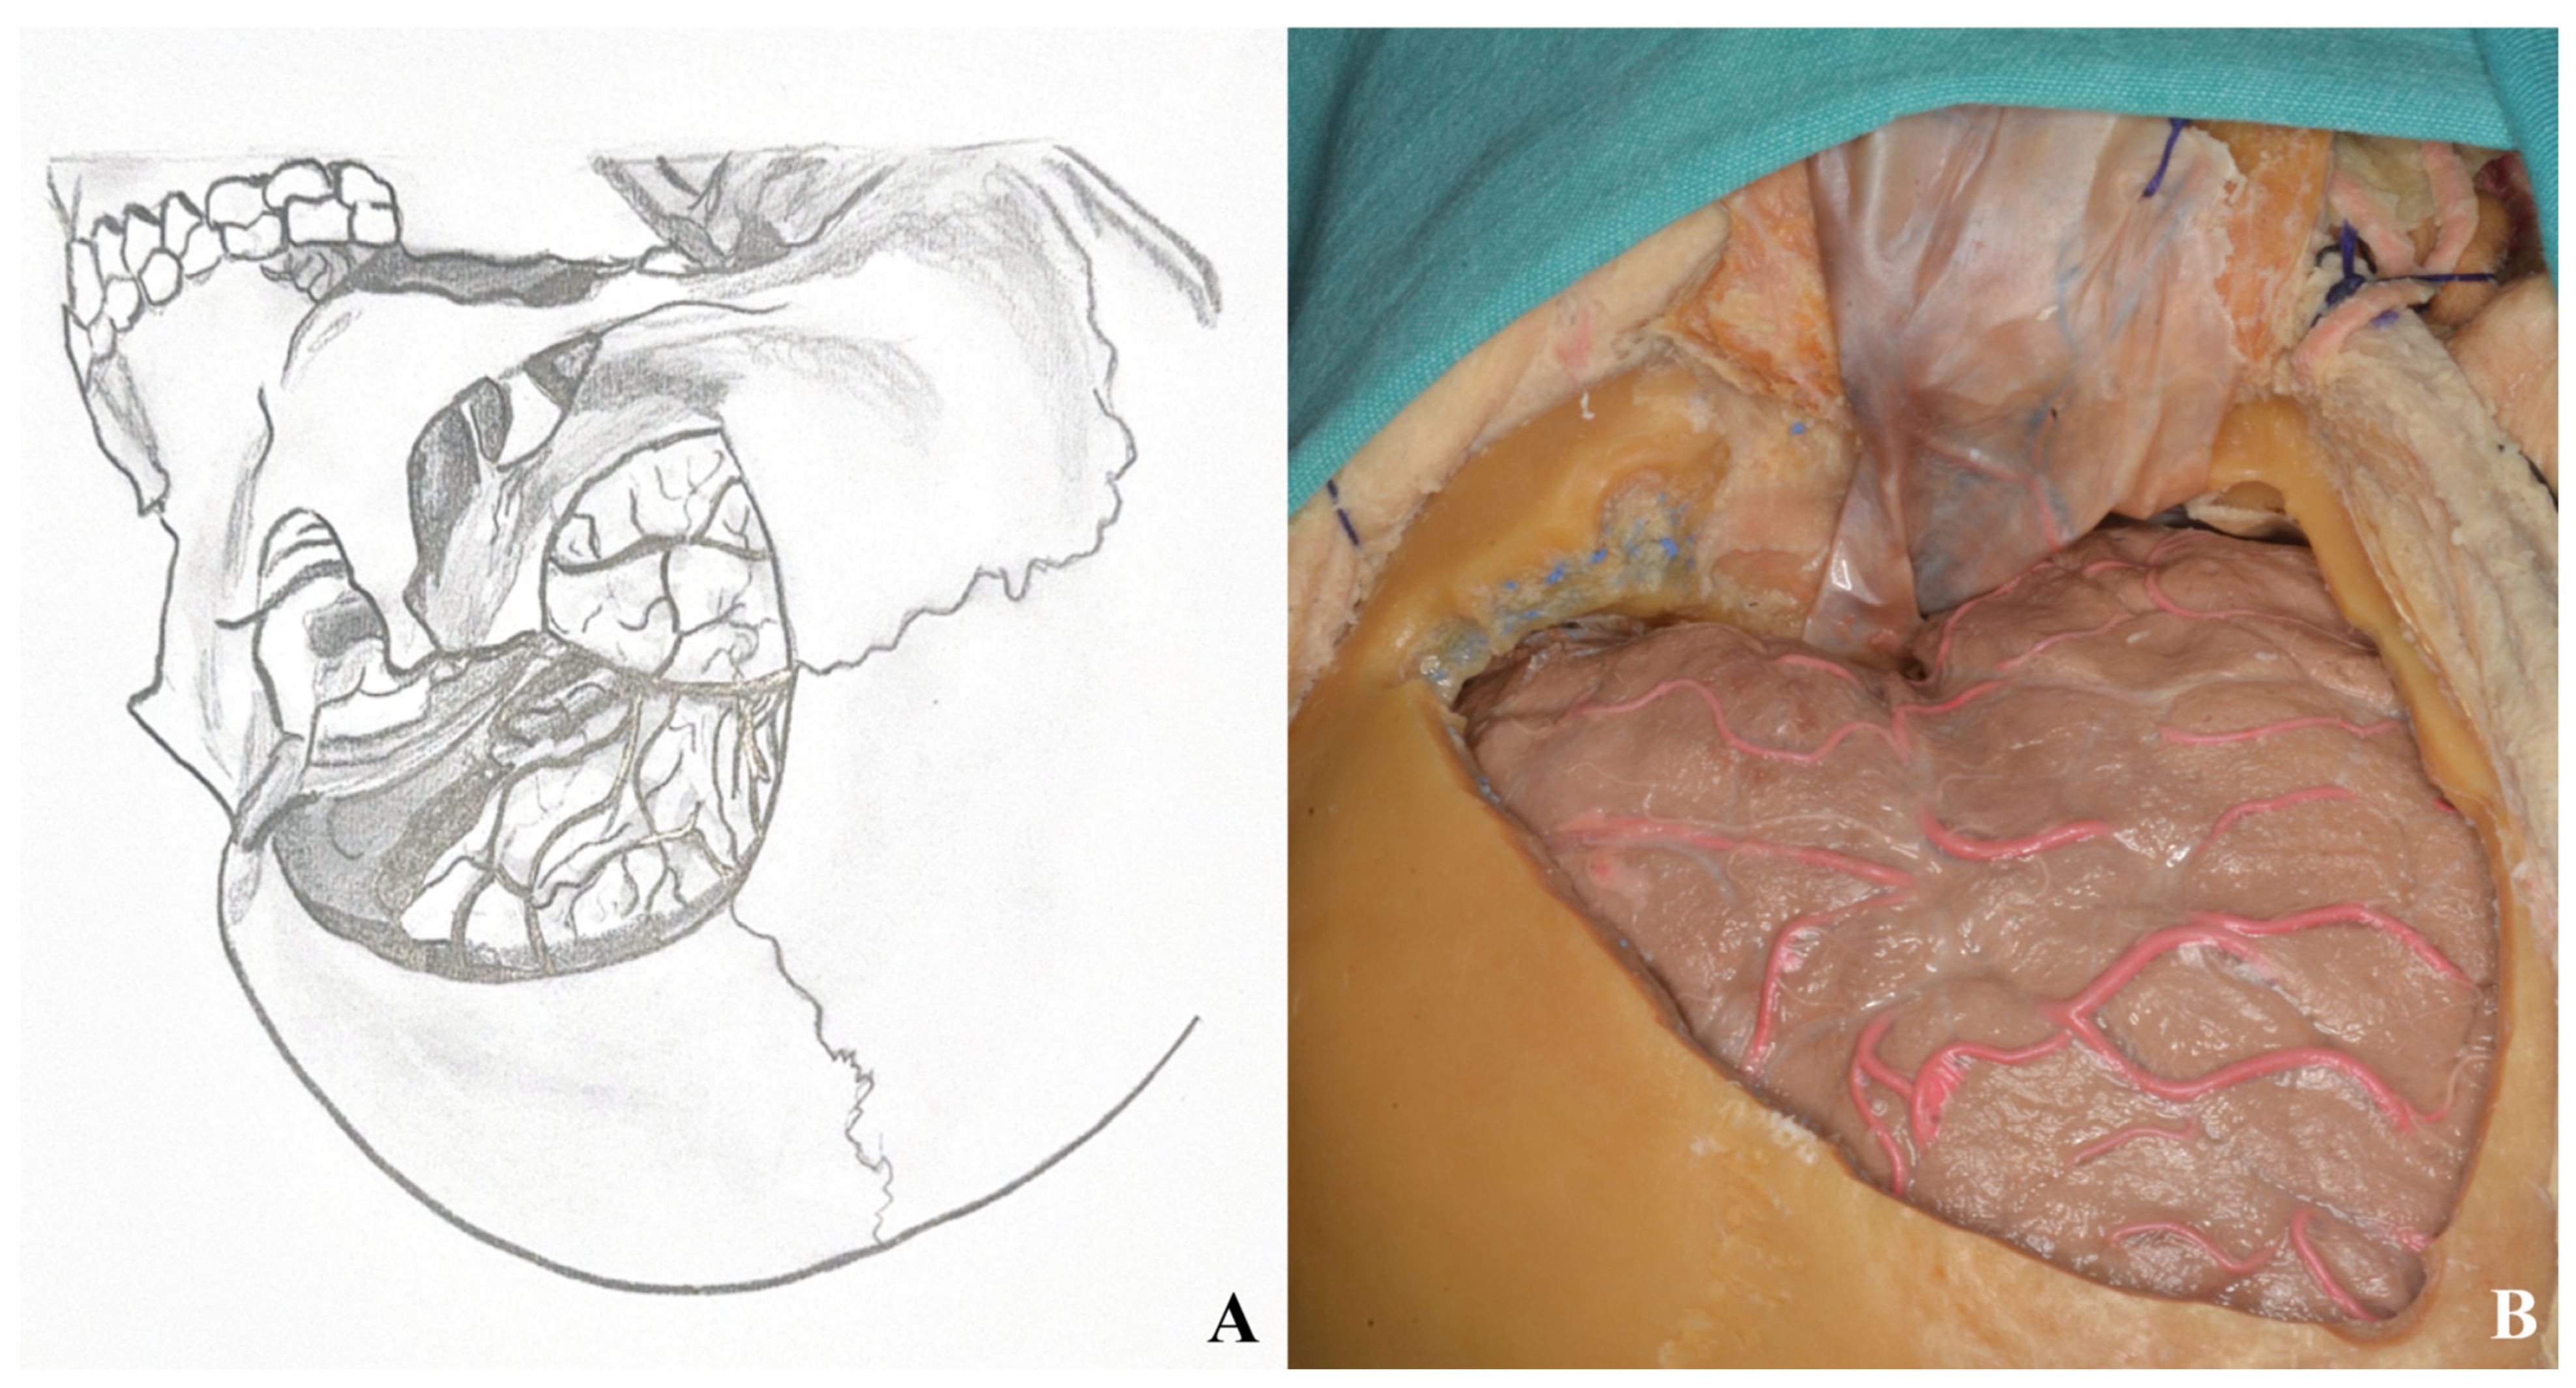

3.2. Orbitozygomatic Approach

3.2.4. Craniotomy

3.2.6. Dura Incision and Sylvian Fissure Opening

3.3. Lamina Terminalis